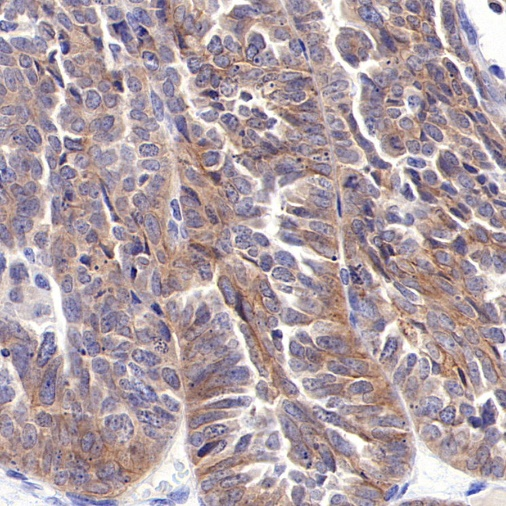

AntBio offers ROR1 recombinant rabbit monoclonal antibodies, which have been validated in human ovarian cancer, gastric cancer, endometrial cancer, and mantle cell lymphoma tissues. These antibodies exhibit higher specificity, sensitivity, and stability, providing more accurate diagnostic results for clinical applications.

Tissue Type: Human Ovarian Cancer